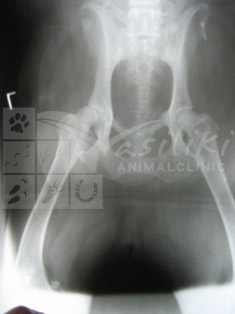

Apart from the radiography performed for diagnostic purposes of pathological conditions, in our clinic we perform examination and radiographic imaging for early detection of hereditary/genetic conditions such as HIP DYSPLASIA, ELBOW DYSPLASIA etc. of large breed dogs.